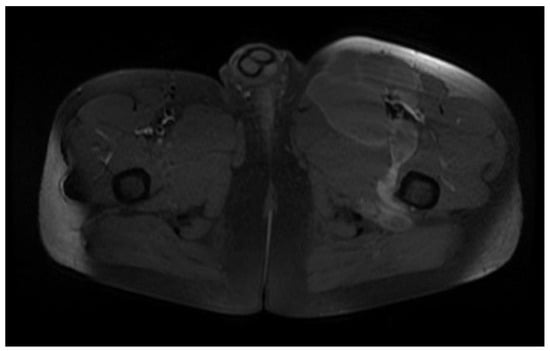

Deep from the gluteus maximus muscle on the left side, there are multiloculated, multiple septate intralesional, relatively well delimited areas, which seem to communicate both with each other and with lesions of a similar appearance located in the thickness and adjacent to the quadratus femoris muscle on the left side, with total dimensions in the coronal plane of approximately 11.3/6.4 cm, with the most likely appearance of parasitic cysts (Figure 19, Figure 20 and Figure 21).

Figure 19.

T2W sequence, axial—Postoperative residual hydatid cyst located at the level of the left psoas muscle and deep to the left gluteus maximus muscle (part 1).

Figure 20.

Figure 21.

T1W +C MRI sequence, coronal—Outstanding hydatid cyst with daughter cells present, located deep to the gluteus maximus muscle on the left side, with peripheral gadolinophilia.